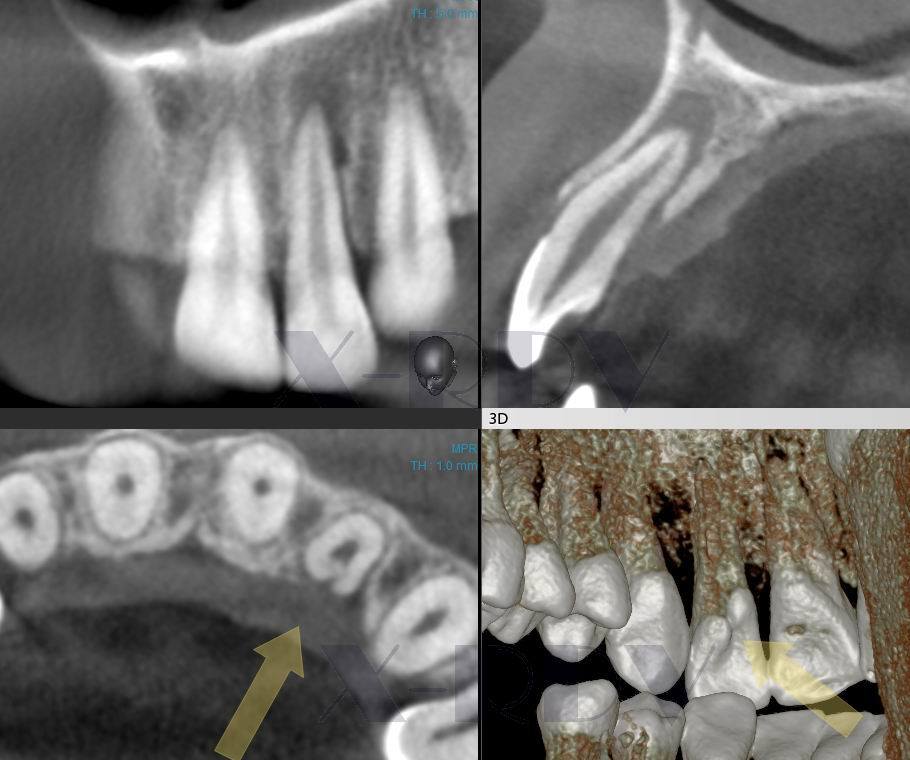

Дентальные снимки и диагностика кариеса